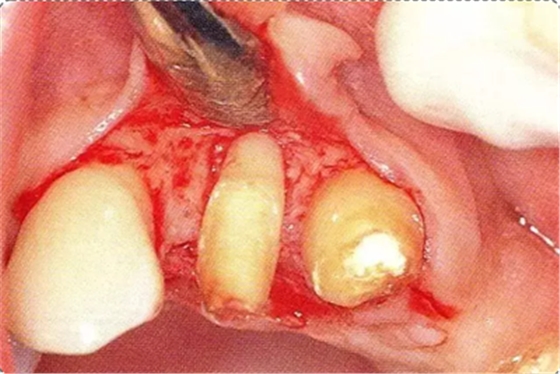

圖10-4 骨缺損部位進行骨修整結(jié)束的狀態(tài)。